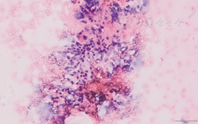

遇标本内血液成分较多时(图26),可以采取以下措施减轻红细胞对镜下观察标本效果的干扰。①将标本分散至数张载玻片,避免单张涂片标本过厚,削弱红细胞对其它细胞的覆盖程度。②穿刺操作时,根据具体情况在抽吸法和非抽吸法之间灵活转换应用。抽吸法穿刺获得标本含血液较多时,可以改为非抽吸法再次穿刺;非抽吸法穿刺获得标本含量较少时,可以改为抽吸法再次穿刺。③采用TCT细胞采集技术,消除红细胞的影响,提高甲状腺结节细胞的观察效果。

专家意见:对于富血供结节,标本中往往难以避免血液成分,应设法减轻红细胞对涂片显微镜下观察的干扰。